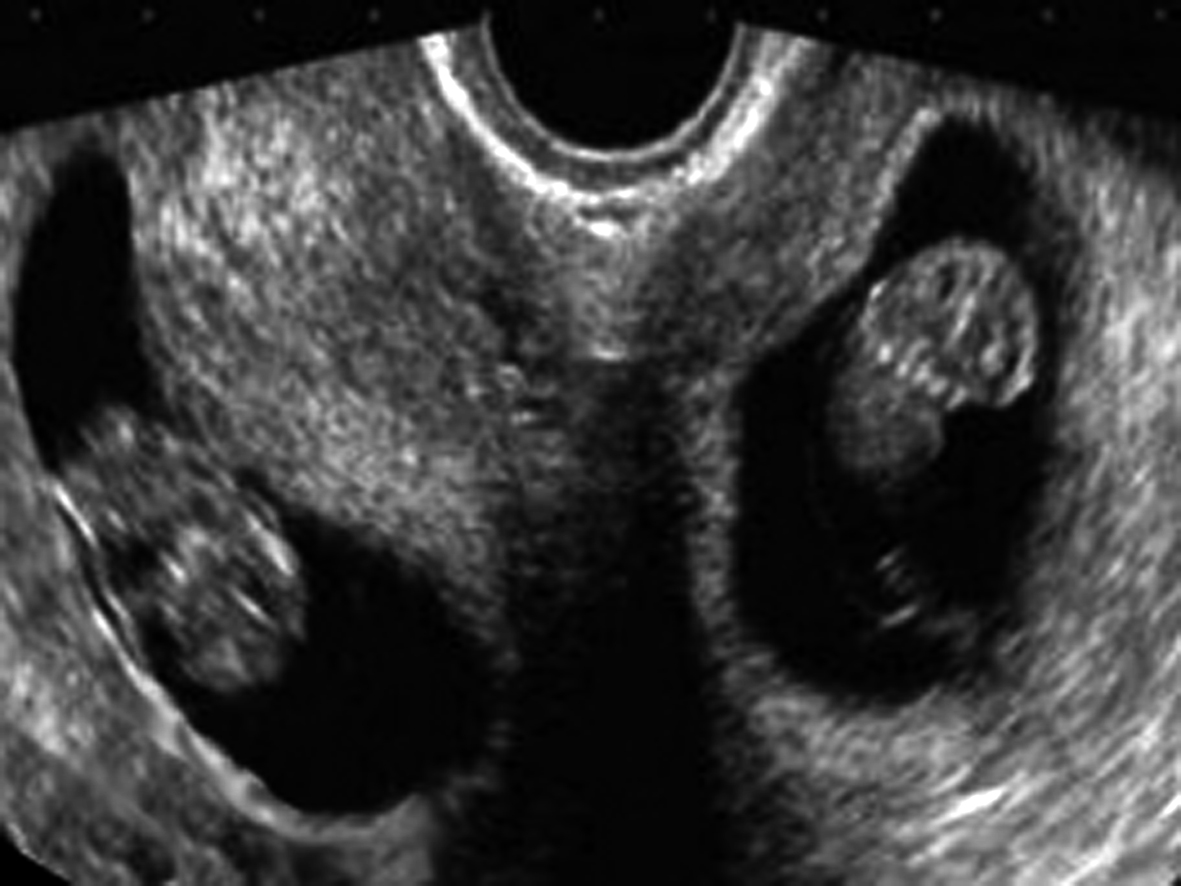

超声检查显示的分离的妊娠囊个数即为绒毛膜囊个数(图1B),两个妊娠囊则提示双绒毛膜囊双胎妊娠,三个妊娠囊即提示三个绒毛膜腔。停经10周时羊膜腔扩大、绒毛膜逐渐变薄,羊膜与绒毛膜融合,超声显像检查对绒毛膜特性评估的难度明显增加。

图1多胎妊娠声像图 A:TVU显示两个孕囊 B:TVU显示5个孕囊